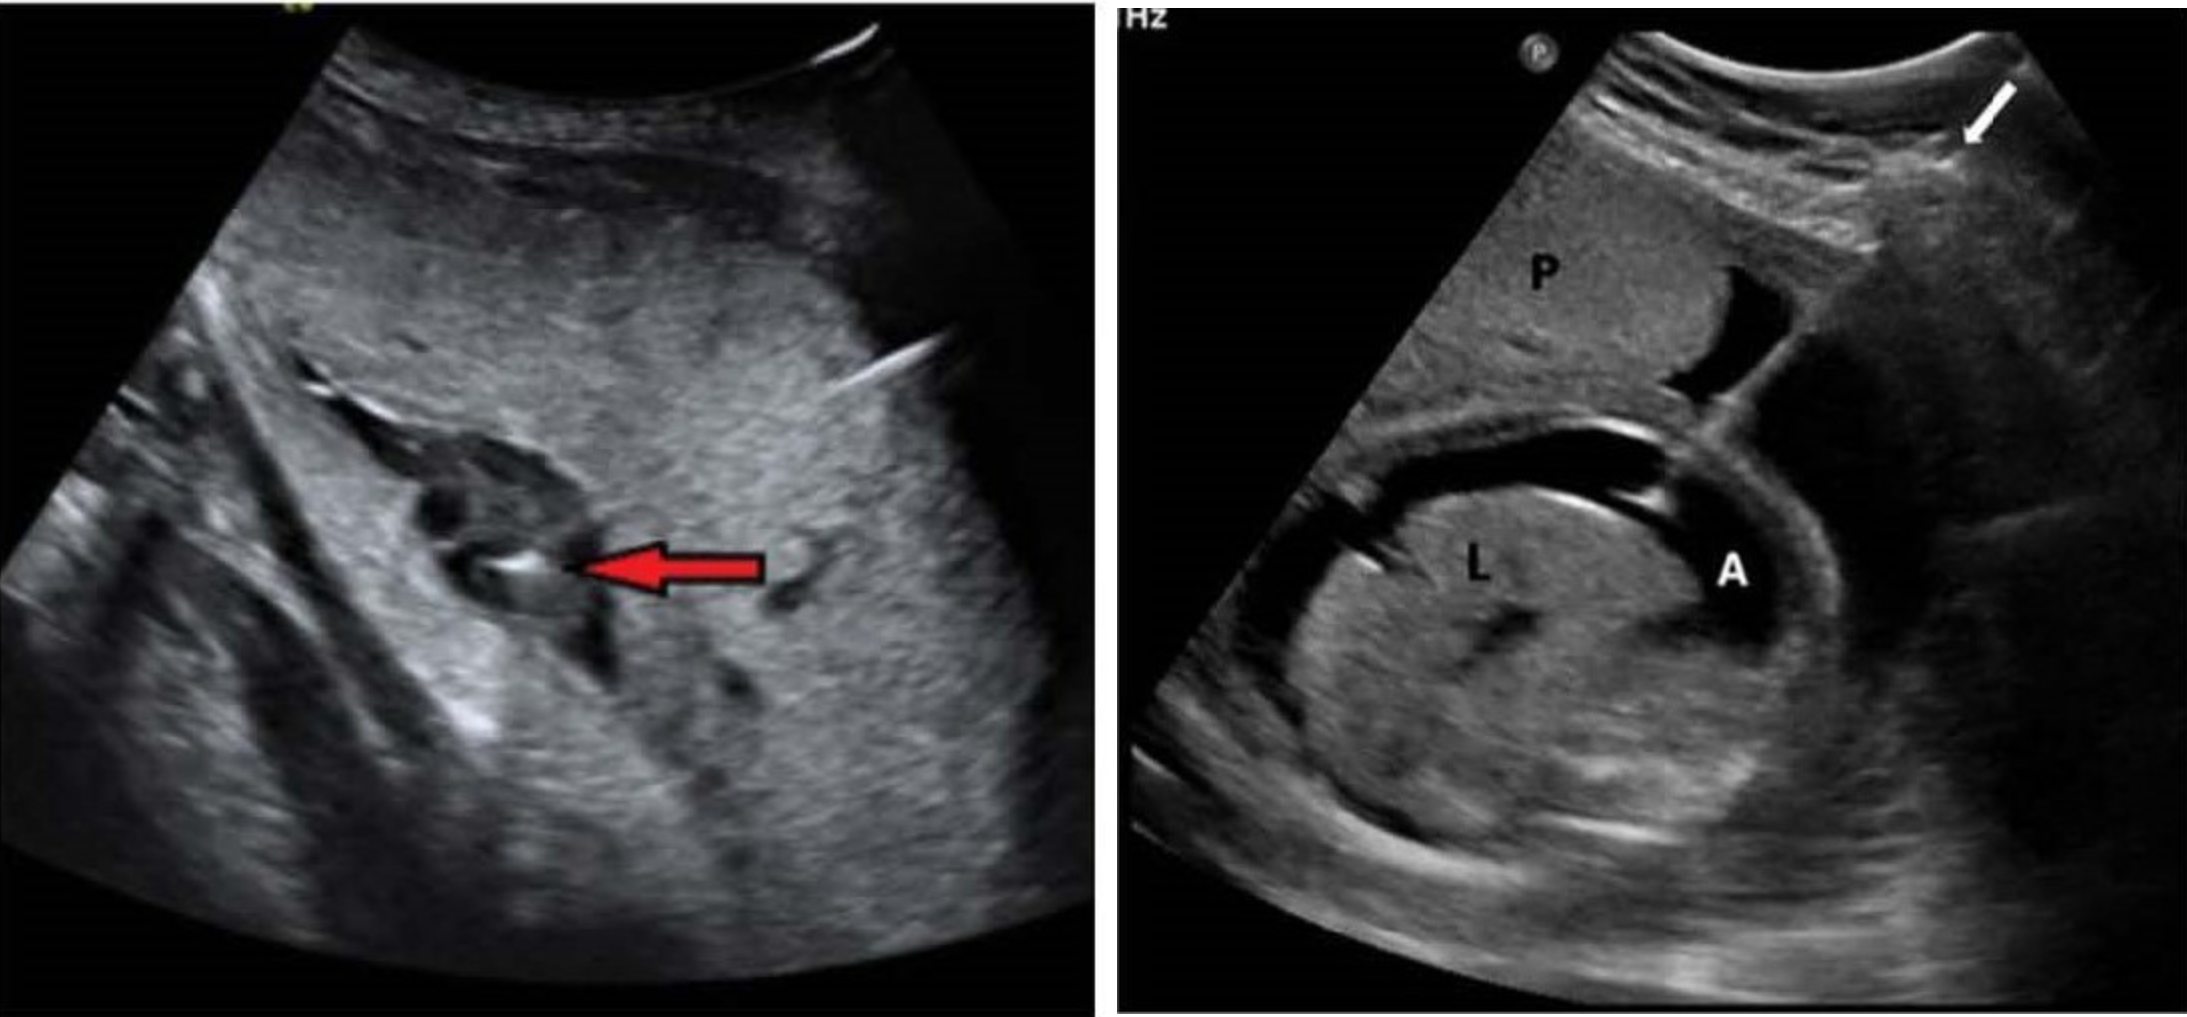

Which image is intravascular and which is intraperitoneal transfusion?

Left is intravascular, right is intraperitoneal